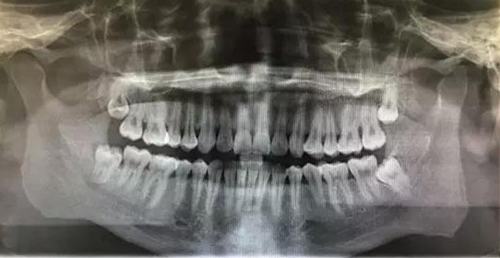

患者,王xx、男,30歲。主訴:右側(cè)下頜后牙牙齦反復(fù)腫痛,要求拔除。??茩z查:48近中頰尖已萌出,牙齦覆蓋牙冠約3/4,遠中有盲袋,牙齦色澤正常,開口度正常。全景片影像檢查:48垂直位,雙根環(huán)抱,遠中有牙囊影。診斷:48中位垂直阻生。治療計劃:建議拔除 48。患者同意拔除,簽術(shù)前知情同意書。

圖1.術(shù)前的全景片影像檢查:48合平面低于47合平面、高于47牙頸部